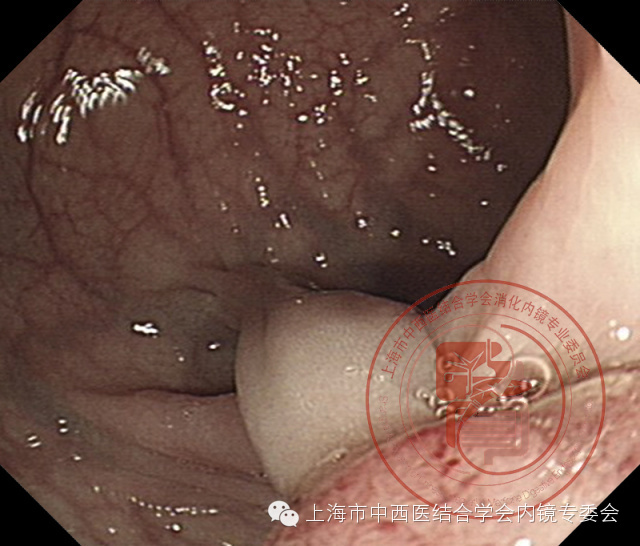

带蒂息肉

阻断蒂部血供